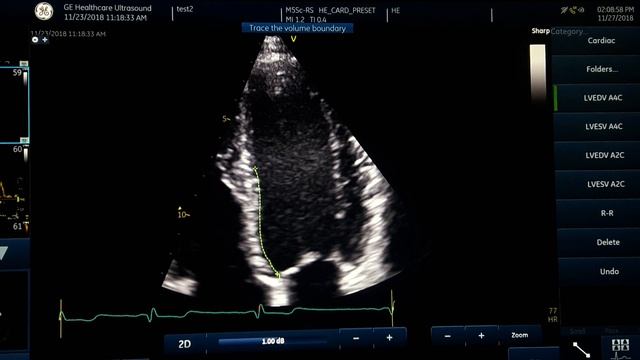

Узи сердца в тагиле

Узи сердца в тагиле 84 фото